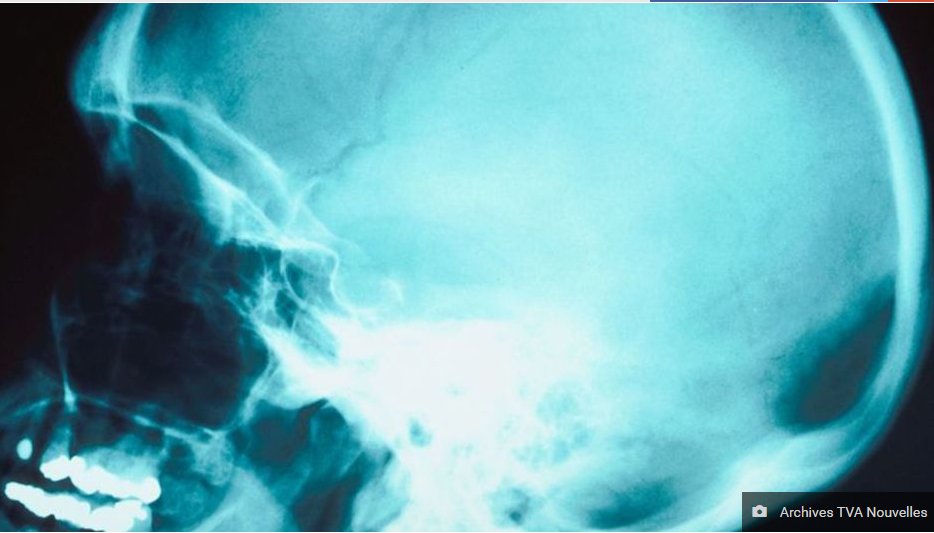

La Société Alzheimer de Montréal vise à aider les personnes atteintes. / The Alzheimer Society of Montréal has been working to help people with Alzheimer's.